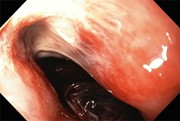

Old technique revisited with surgical innovation: complicated Mallory–Weiss tear with bleeding gastric ulcer exclusion

Osamu Yoshino and others

Journal of Surgical Case Reports, Volume 2016, Issue 1, January 2016, rjv173, https://doi.org/10.1093/jscr/rjv173